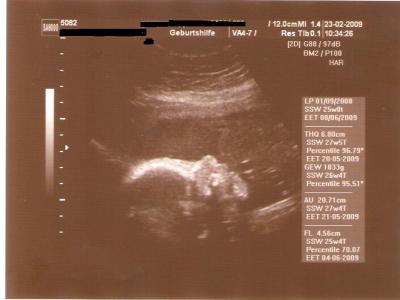

Würmchen ist nun 20,71 cm groß und wiegt 1033 Gramm. Eigentlich nix zu dem, was ich zugelegt habe ;-)

Laut meiner Waage sind es bereits 7 kg, beim Arzt waren es allerdings nur 5,5 kg. Und da mir letzteres besser gefällt (klingt ja auch viel besser), lass ich nun das mal gelten ;-) Will ja mal nicht so sein.

Würmchens Oberkörpergröße liegt im oberen Normbereich. Ist aber noch kein Grund zur Besorgnis. Herr oder Frau Junior ist momentan halt etwas gut beinander (liegts an der Haselnuss-Creme?? (auch hier nenne ich den Namen des Produktes nicht ;-) )